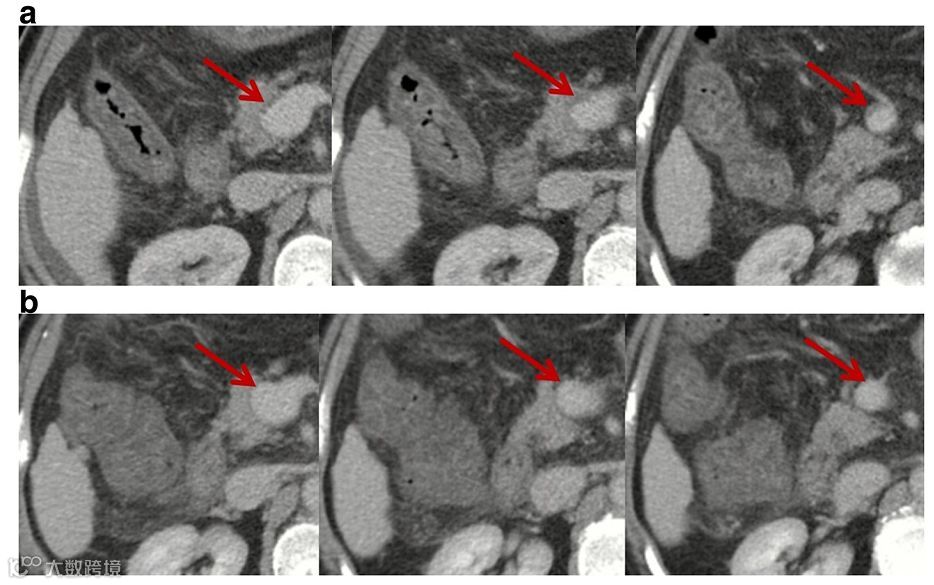

文章展示了祁兴顺医生收治的两例肝硬化“一过性”门静脉血栓患者的影像学结果(如下图)。

第1例患者

图a:门静脉主干与脾静脉汇合处的血管壁可见少许血栓。图b:门静脉主干与脾静脉汇合处的血管腔内通畅。

第2例患者

2016年3月至7月期间,门静脉主干与脾静脉汇合处血栓呈逐渐加重趋势。然而,2017年5月及9月的两次影像学检查均提示,门静脉主干与脾静脉汇合处血栓消失。